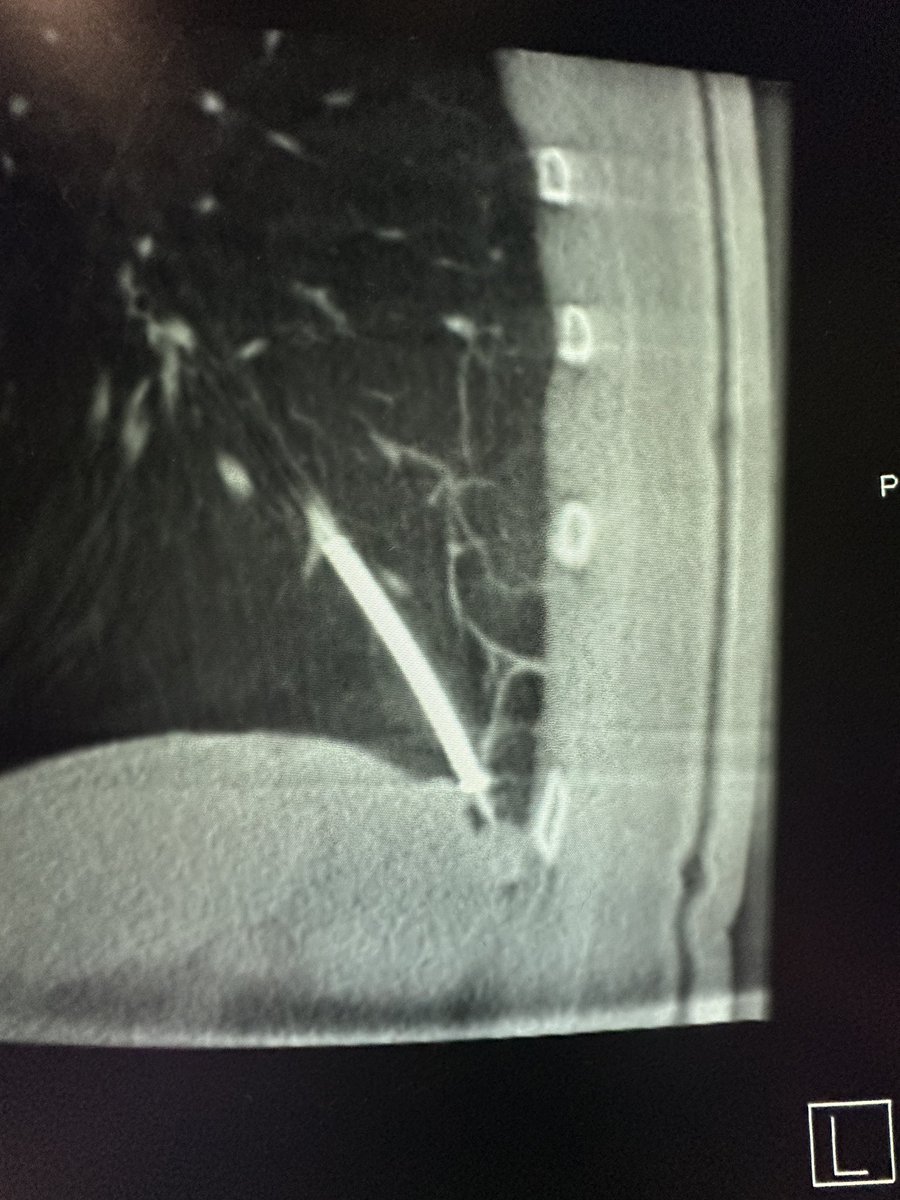

Bhadra & Condra CBCT Bronchoscopy

If you don't like the road you are on, pave a new one: Cone Beam CT Bronchoscopy.